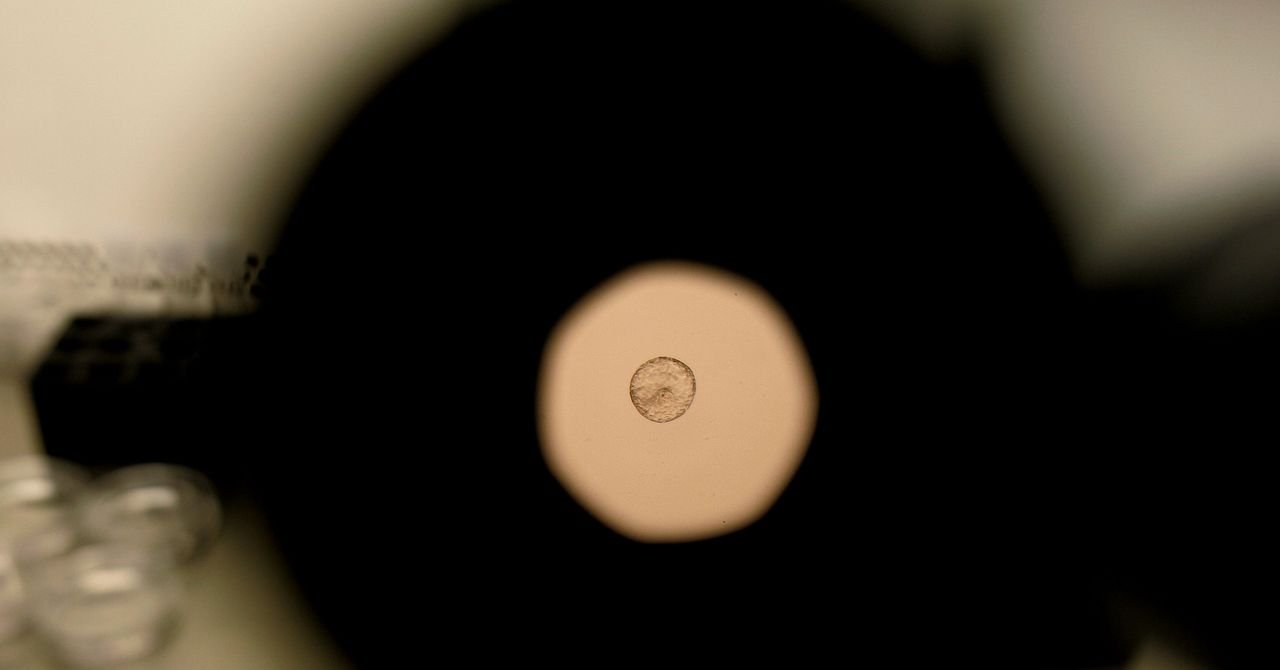

The simulation made it possible to praise how a human fetus not only adhered to the uterus lining, but actively insert itself. “We noticed that the embryo was drawn to the uterus matrix, it was running and reconstructing,” the research assistant Amelie Gadau explained, which was published The progress of scienceThe

Time-laps video of the mouse embryo (left) and the implantation process of a human embryo (right).

The human fetus used in this study provided Dexiece Muzar Barcelona, ​​a female health clinic that specialized in processes, gynecology and reproductive medicine. “Our job is to provide technical advice and to the human fetus strictly selected for research, confirming that they have met the ideal conditions of this project,” said Mikel Soli, director of the Dexius Mazer Creopageration Laboratory.